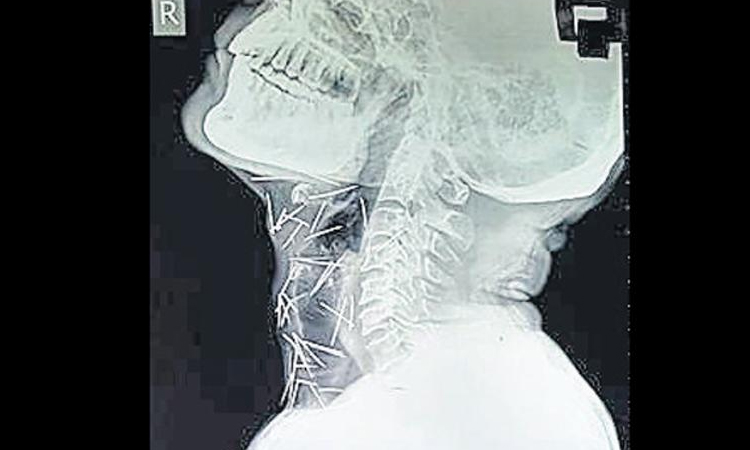

ശരീരത്തിൽ 75 പിന്നുകളുമായി ഒരു മനുഷ്യൻ

text_fieldsജയ്പൂർ: പിന്നുകൊണ്ട് നിർമിച്ച മനുഷ്യ കുഷ്യൻ എന്നു വിളിക്കാം രാജസ്ഥാൻ സ്വദേശി ബദ്രിലാൽ മീണയെ. 75 പിന്നുകളാണ് 56കാരനായ ബദ്രിലാലിെൻറ ശരീരത്തിൽ നിന്ന് കണ്ടെത്തിയത്. കഴുത്ത്, കൈത്തണ്ട, കാലുകൾ എന്നീ ഭാഗങ്ങളിൽ തൊലിക്കടിയിലായാണ് പിന്നുകൾ കാണപ്പെട്ടത്.

ഒരിഞ്ചോളം നീളമുള്ള പിന്നുകൾ ശരീരത്തിലെത്തിയതെങ്ങനെ എന്ന് വ്യക്തമാകാതെ കുഴങ്ങിയിരിക്കുകയാണ് ഡോക്ടർമാർ. പിന്നുകൾ കുത്തിക്കയറ്റിയ അടയാളങ്ങളൊന്നും ശരീരത്തിലില്ല. വിഴുങ്ങിയതല്ലെന്ന് ഡോക്ടർമാർ ഉറപ്പിച്ചു പറയുന്നു.

വയറിലോ, ആമാശയത്തിലോ, െചറുകുടലിലോ പിന്നുകൾ കണ്ടെത്താത്തതിനാൽ വിഴുങ്ങിയതല്ലെന്ന് ഉറപ്പിക്കാമെന്നാണ് ഡോക്ടർമാരുടെ പക്ഷം.

റെയിൽവേ ജീവനക്കാരനായ ബദ്രിലാലിനുമറിയില്ല എങ്ങനെയാണ് പിന്നുകൾ ശരീരത്തിലെത്തിയതെന്ന്.

വലതുകാലിലെ വേദനക്കും പ്രമേഹത്തിനും ചികിത്സക്കായി കോട്ടയിലെ സ്വകാര്യ ആശുപത്രിയിൽ സ്കാനിങ്ങ് നടത്തിയപ്പോഴാണ് സംഭവം ശ്രദ്ധയിൽ പെട്ടത്.